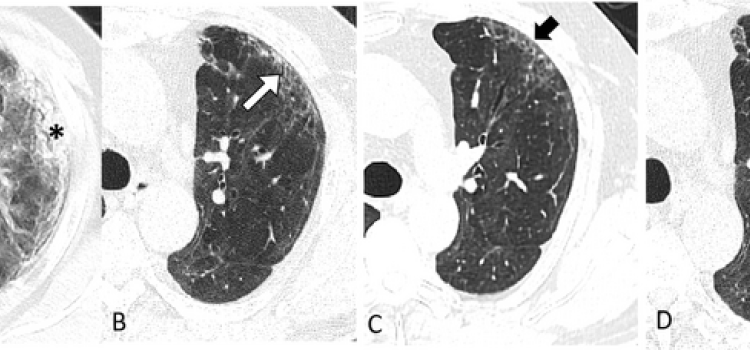

News and new technology innovations concerning how imaging technology for the lungs. This includes computed tomography (CT), X-ray and ultrasound imaging of the lungs to diagnose and monitor treatment for lung cancer, COPD, pulmonary embolism (PE), pneumonia, tuberculosis and COVID-19 can be found on this channel.

Nov. 3, 2025 — RevealDx, a leader in the characterization of lung nodules, has introduced MDR Certification of RevealAI ...

Aug. 26, 2025 — Optellum, a global leader in AI for lung health, recently announced the world’s first thorax CT ...

July 3, 2024 — Results from a new study led by researchers at The University of Texas MD Anderson Cancer Center support ...